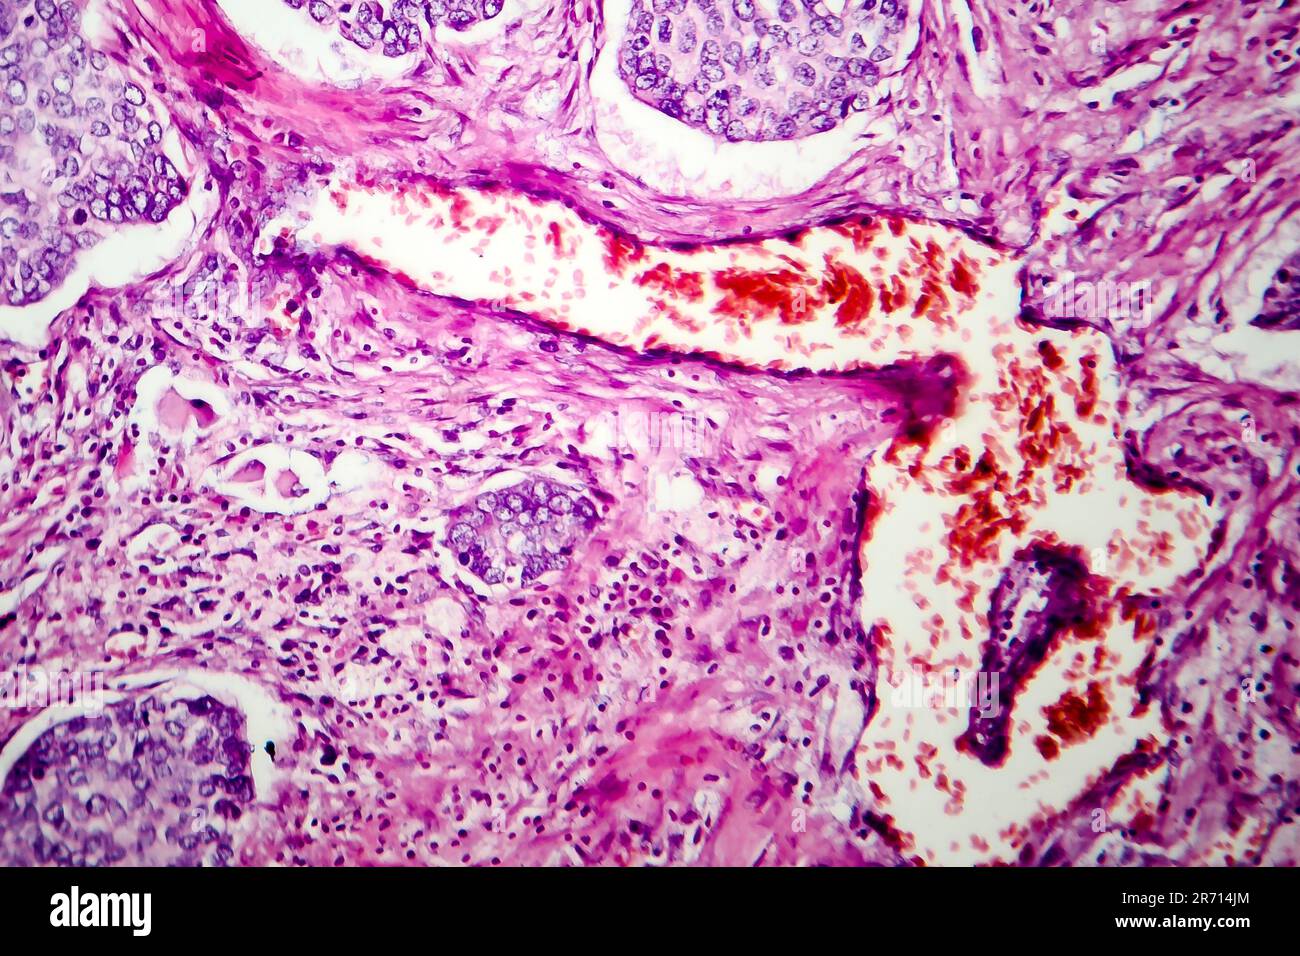

Adénocarcinome pulmonaire in situ mucineux